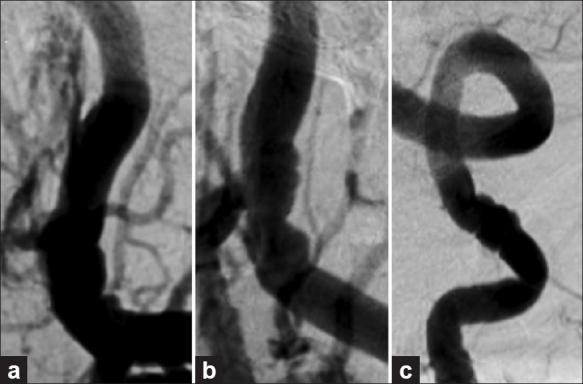

Here we describe a case of isolated or primary IVH (PIVH) in a 71-year-old woman presenting with severe headache. Emergent catheter cerebral angiography, performed after nondiagnostic computed tomography angiography (CTA), revealed the bleeding source to be a 4 × 2.6 mm distal medial lenticulostriate artery aneurysm that ruptured directly into the lateral ventricle. The poorly accessible location of the aneurysm for both endovascular and direct surgical treatment argued for conservative management. A good clinical outcome was obtained with rapid angiographic resolution of the ruptured aneurysm.

在此,我们描述一例71岁女性的孤立性或原发性脑室内出血(PIVH)病例,该患者表现为严重头痛。在非诊断性计算机断层扫描血管造影(CTA)后进行的急诊导管脑血管造影显示,出血源为一个4×2.6毫米的豆纹动脉内侧远端动脉瘤,该动脉瘤直接破裂入侧脑室。该动脉瘤对于血管内治疗和直接手术治疗而言位置不佳,因此主张保守治疗。随着破裂动脉瘤快速血管造影消退,获得了良好的临床结果。